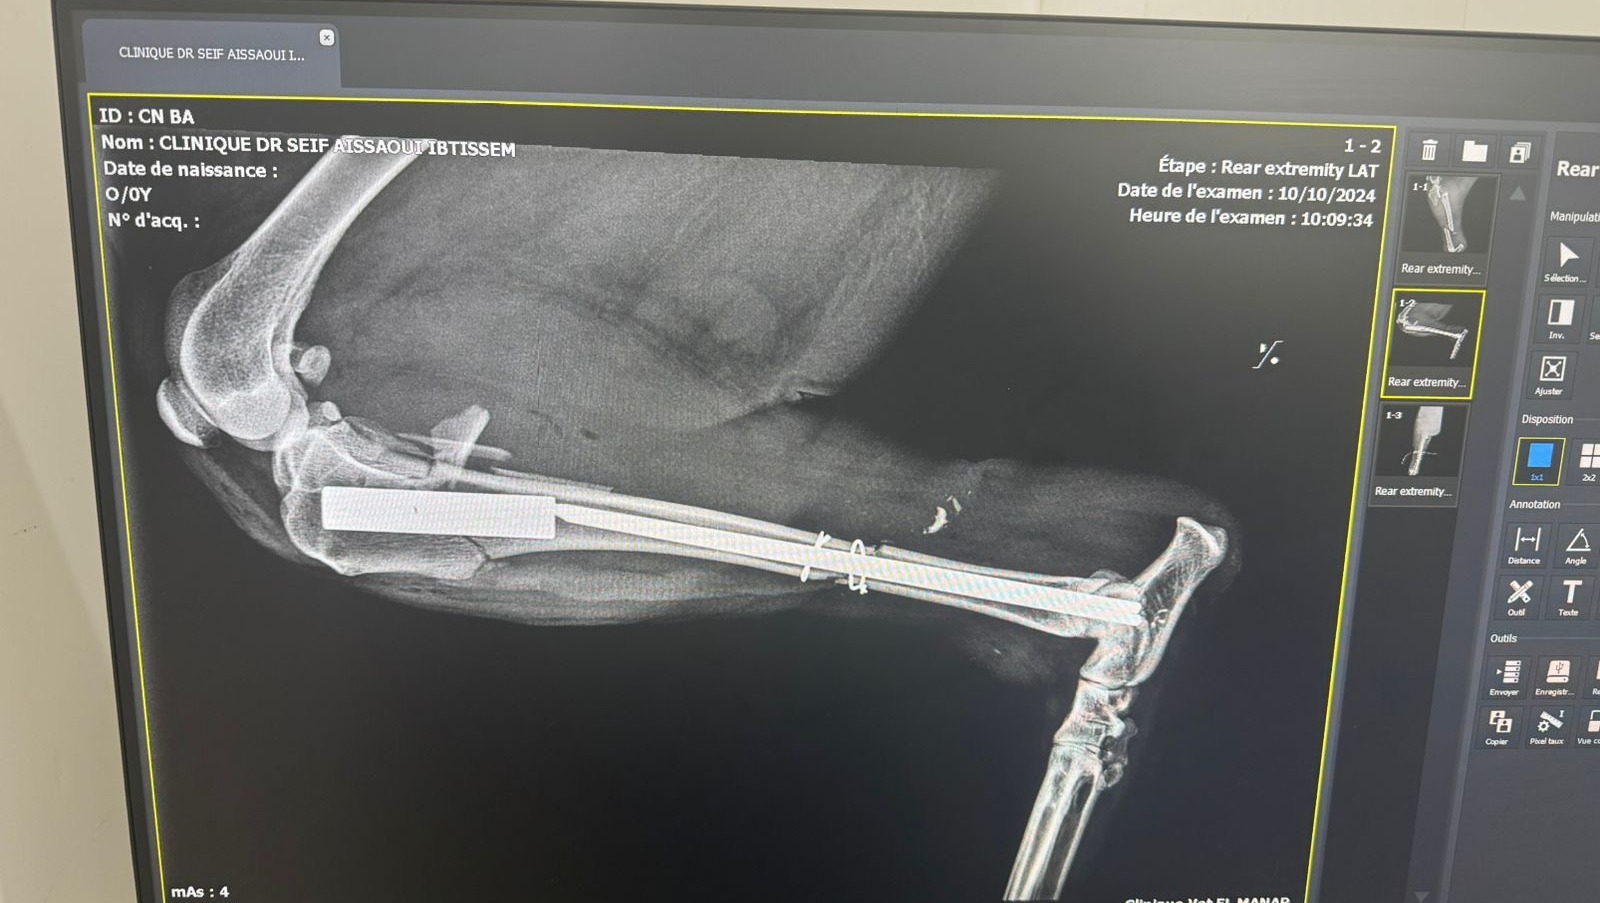

Comme vous pouvez le voir les animaux que nous aidons sont victimes de graves blessures nécessitant des soins vétérinaires très importants.

Ces chiens sont handicapés à vie — certains ont perdu une patte, d’autres deux, certains vivent avec une mâchoire arrachée ou la colonne vertébrale brisée. Malgré leur souffrance, ils nous montrent chaque jour leur incroyable courage et leur soif de vie.

Nous avons déjà investi beaucoup d’argent pour sauver ces chiens de la mort ou d’une vie dans d’horribles souffrances. Aujourd’hui, nous avons besoin de vous pour continuer financer leurs soins vétérinaires : opérations chirurgicales, traitements lourds, rééducation, médicaments, nourriture spécifique… Chaque geste compte pour leur offrir une seconde chance.